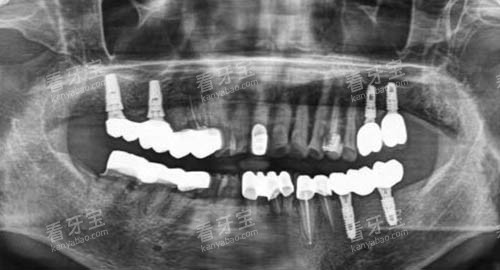

对于成人患者,亮贝美口腔提供了种植牙、牙齿矫正、牙齿美白、牙周治疗等多种项目。

医院引进了较高的种植牙技术和设备,能够为患者提供更加可靠、有效的种植牙服务。